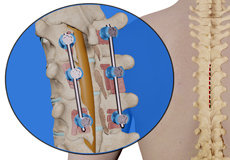

Posterior Lumbar Fusion

Spinal fusion, also called arthrodesis, is a surgical technique used to join two or more vertebrae (bones) within the spine. Lumbar fusion is the fusion the vertebrae in the lumbar portion of the spine (lower back).

Posterolateral Lumbar Fusion

Posterolateral lumbar fusion is a surgical technique that involves correcting spinal problems from the back of the spine by placing bone graft between segments in the back and leaving the disc space intact.

Lumbar Interbody Fusion

Lumbar interbody fusion (LIF) surgery is a surgical technique that involves the removal of a damaged intervertebral disc and the insertion of a bone graft into the disc space created between the two adjoining vertebrae. Bone grafts promote healing and facilitate fusion. Screws and rods are used to stabilize the spine during the healing process.

Spinal Fusion

Spinal fusion is the surgical technique of combining two or more vertebrae. A fusion of the vertebrae involves the insertion of secondary bone tissue obtained either from an autograft (tissues from your own body) or allograft (tissues from another person) to enhance the bone healing process.